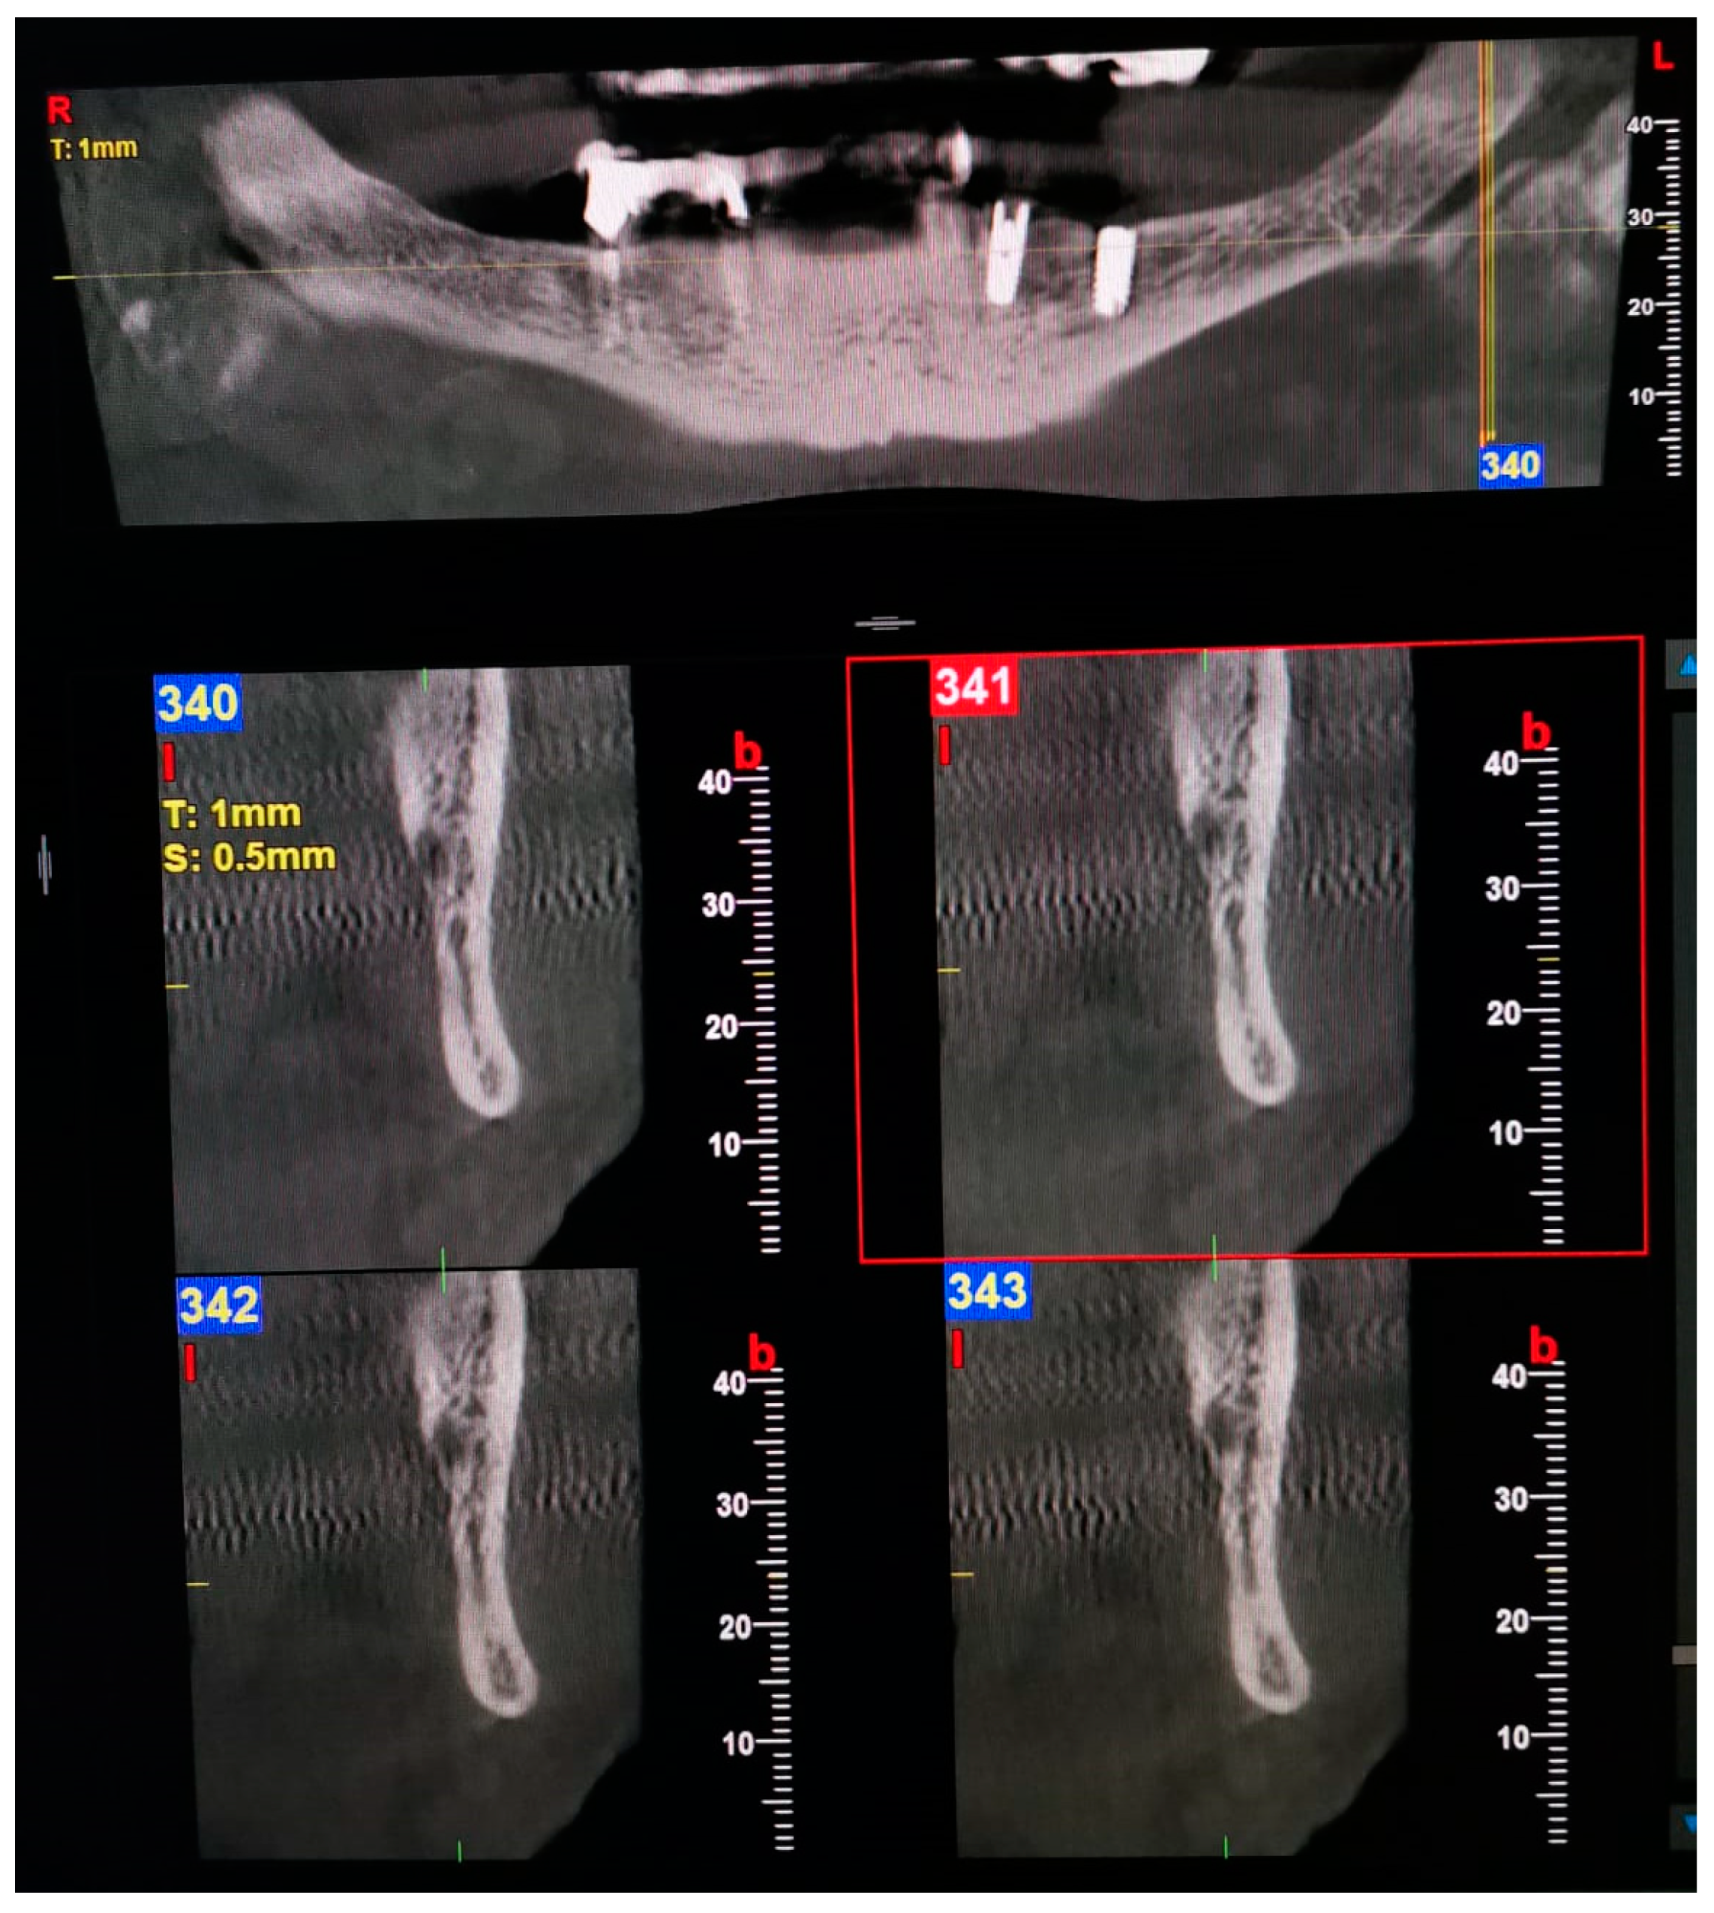

| 3—Forward | Without confluence: The forward canal, which bifurcates from the mandibular canal in the mandibular ramus region, courses forward to the second molar region.  With confluence: The forward canal, which bifurcates from the mandibular canal in the mandibular ramus, courses anteriorly and then rejoins the main mandibular canal.  |